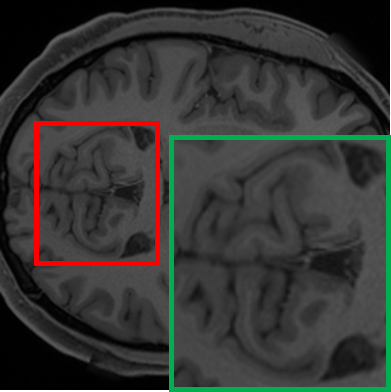

Refer to caption

(a) 1.5T

(b) 3T

(c) 7T

Figure 1: An example of axial view brain MR scans at 1.5T, 3T, and 7T field strengths.